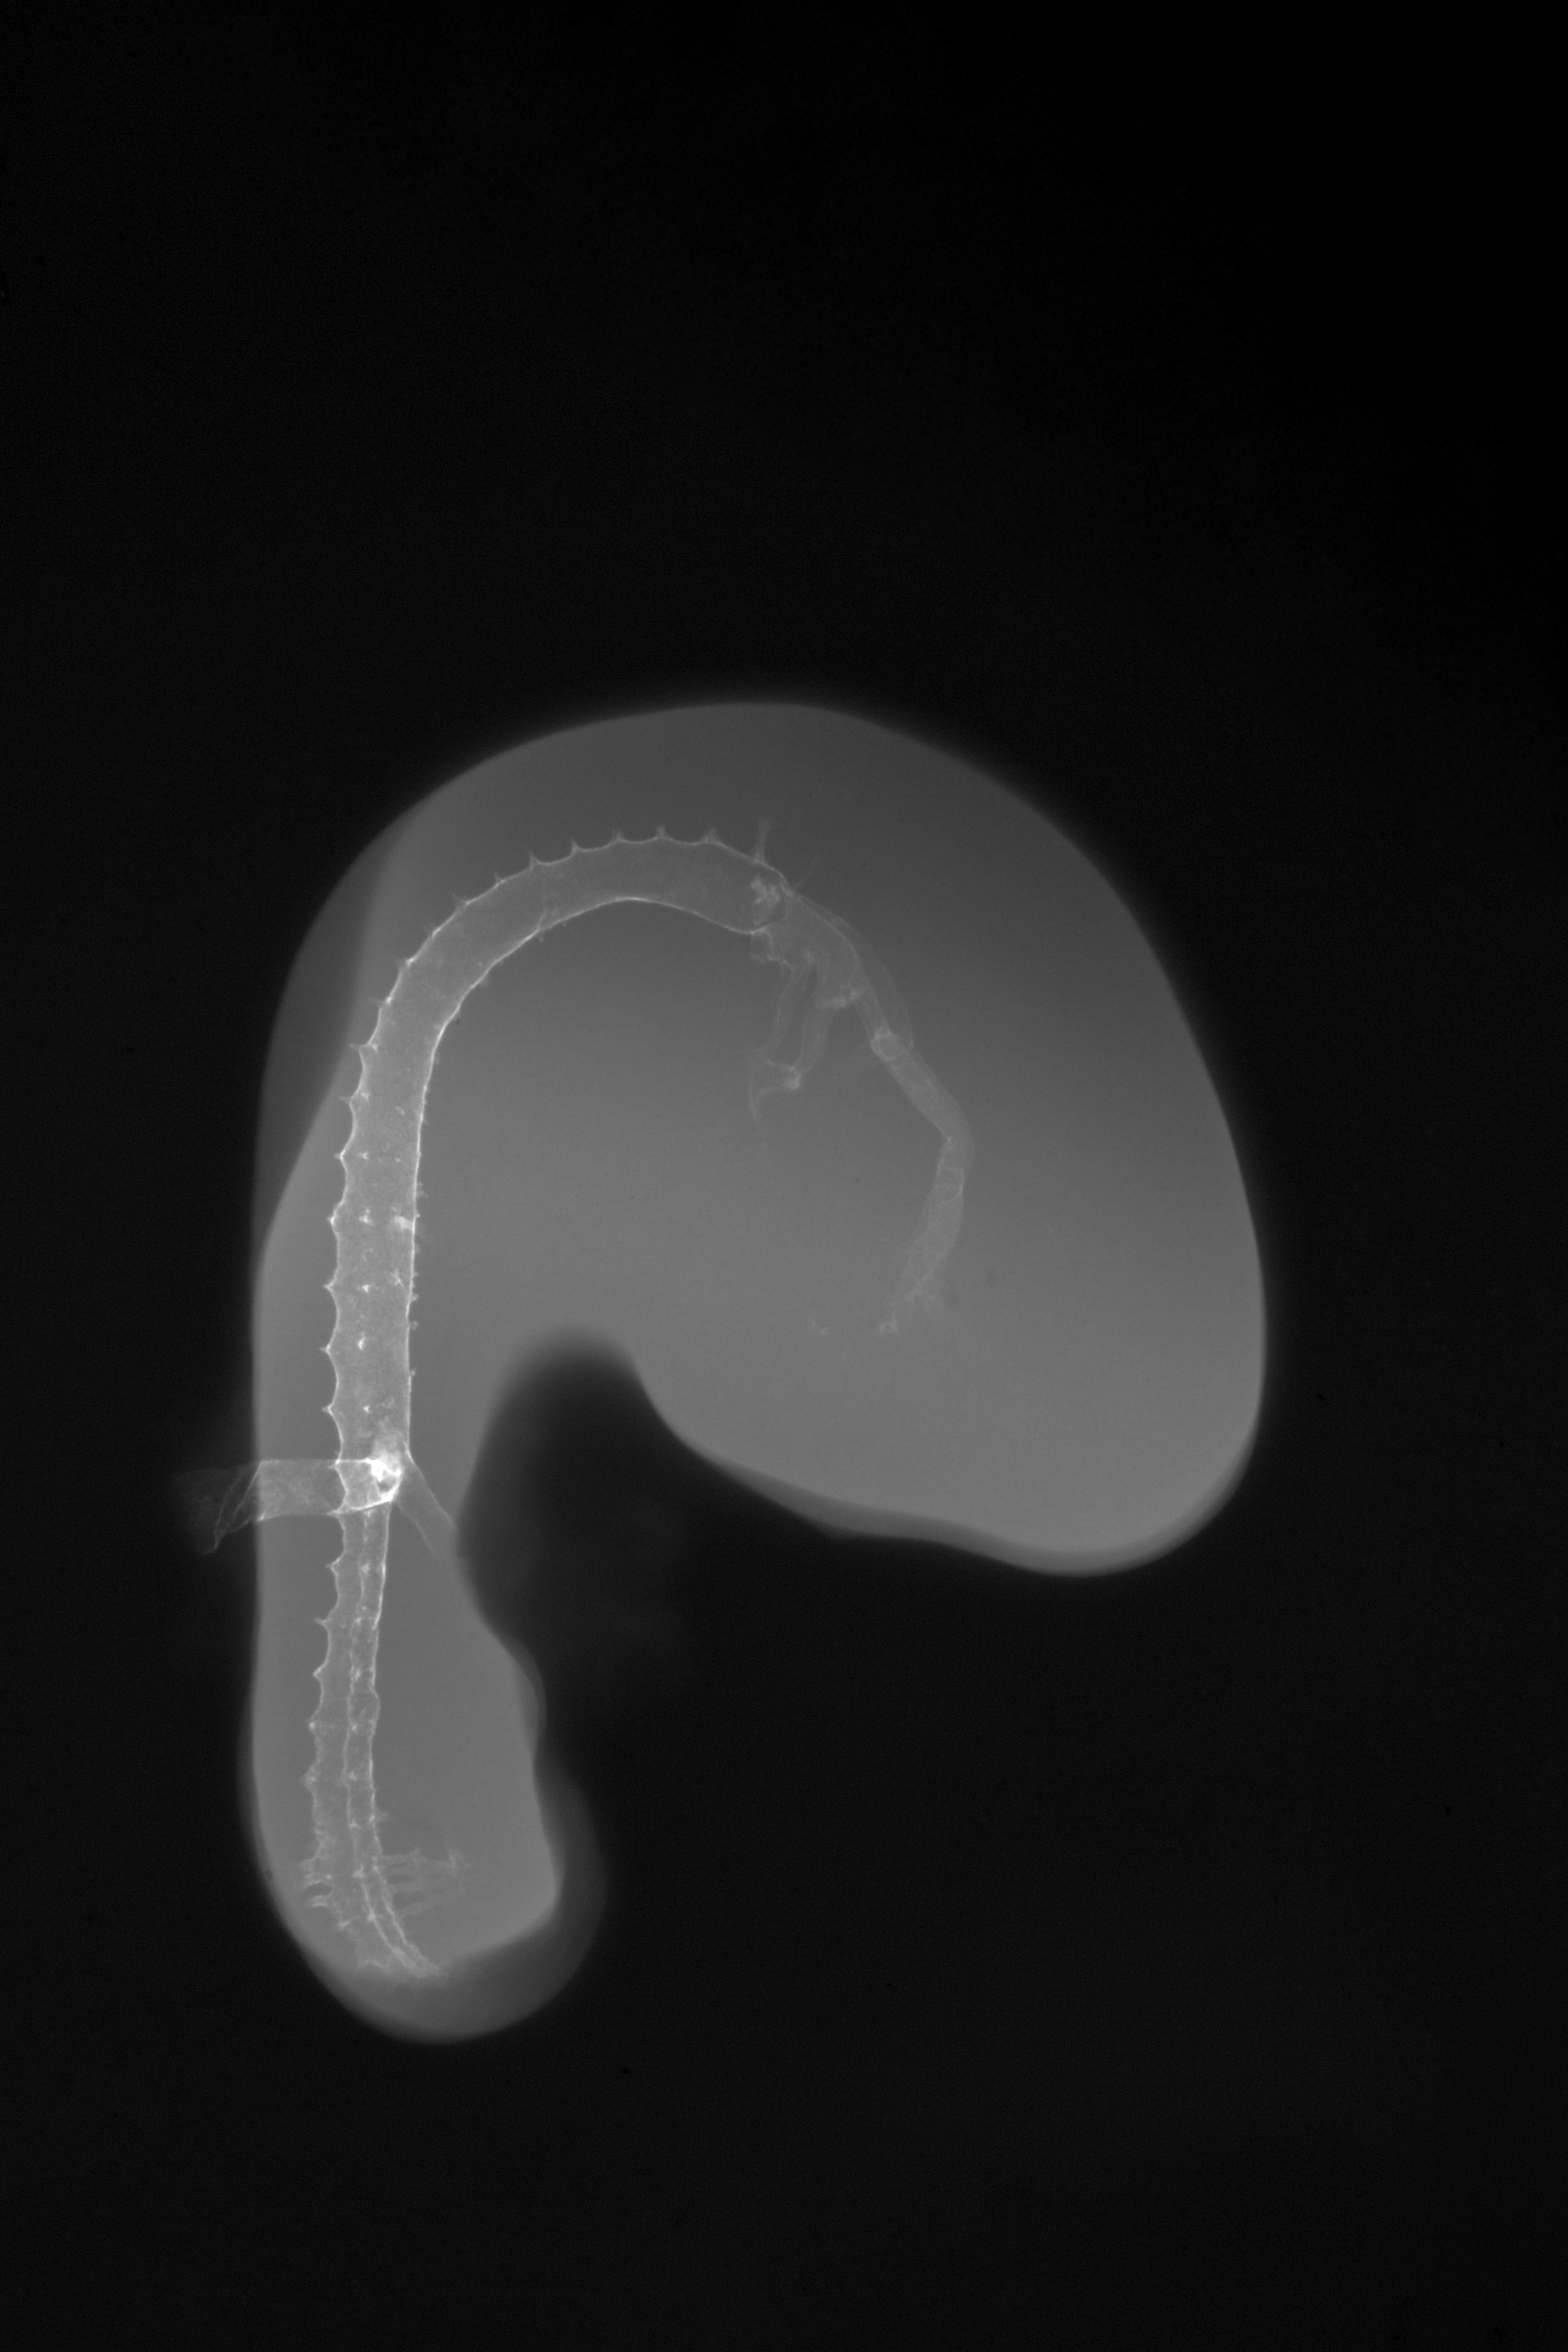

Chick Embryo Microangiography

Hamburger-Hamilton (HH) Stage 19 (approx. 3 - 3.5 days)

X-Ray Micrographs